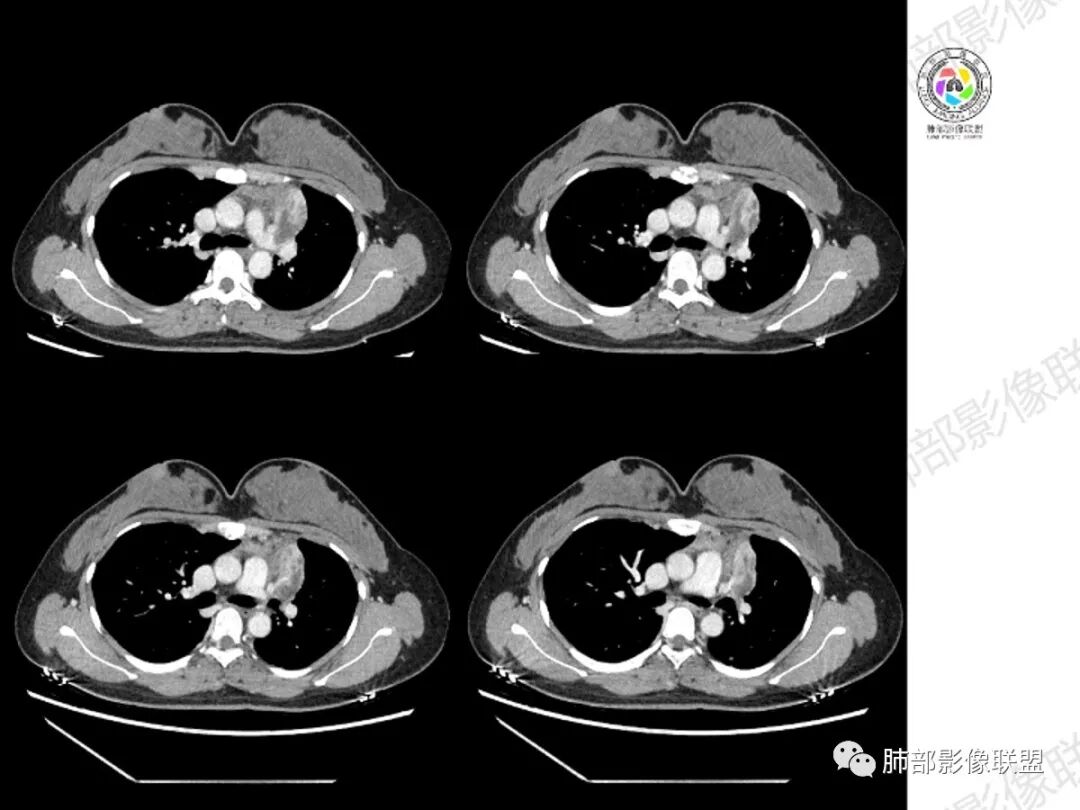

年轻女性,慢性病程,左上叶纵隔旁大片实变,心脏纵隔左移,左主及左上叶支气管变窄呈针孔样,实变内可见斑点状钙化,显著不均匀强化,内可见低密度粘液拴,显著强化不支持TB,左上叶不张在腺癌少见,综合病变部位及强化表现考虑粘液表皮样癌,其次考虑类癌

女性,29岁,咳嗽咳痰,痰中带血1月余,CT示左肺尖胸膜下纵隔旁不规则实变影,内部可见小点状钙化灶,支气管略狭窄,增强可见低密度不强化区,粘液栓?实性成分明显不均匀强化,局部与左肺动脉分界不清,另左肺可见多发小结节,考虑为恶性,黏表可能,鉴别结核

年轻女性,咳嗦咳痰伴咳血1月多,ct可见纵隔左移,左肺容积减小,左肺上叶可见一不规则实变影,朝肺内侧边界清楚,部分边缘与纵隔界限模糊,临近支气管堵塞,内见点状钙化,增强不均匀强化,内可见多个低密度区,粘液?并与左肺动脉界限模糊,似受侵,考虑恶性,黏表?但病灶远端有多发小结节,卫星灶?结核待排

分隔样强化,符合粘液栓或干酪坏死,边界锐利清晰,剩下强化明显的部分有不张的肺组织

胸部CT:左肺体积缩小,左肺上叶前段纵隔旁胸膜下大片实变影,边缘清楚、匀齐、平直收缩,部分略膨隆,周围多发结节、树芽卫星灶,纵隔窗病灶与纵隔胸膜黏连,实变内多发点状钙化。平扫密度尚均匀,增强扫描不均匀明显强化,多个低密度区,呈仙人掌样,伴有条状血管影,考虑慢性炎症伴左上叶前段支气管闭塞,TB?鉴别黏表、腺癌等。

青年女性、痰血症状一月,左胸廓缩小,左上肺固有段支气管狭窄堵塞,前段支气管扩张伴粘液栓、远侧肺不张,肿块整体呈梭形沿前段支气管爬行向外延伸,内可见多处圆形低密度坏死灶,肺不张处血管造影强化明显,周围散发束状细小结节灶,肺门及纵隔淋巴结尚正常。考虑结核可能大。

左上叶支气管堵塞,腔内粘液栓,粘液栓不强化,远端不张实变

周围多发小斑片,病灶内可见点状钙化,29岁女性,警惕结核;

如果粘液栓强化,警惕癌,年轻女性,多为类癌、黏液表皮样癌